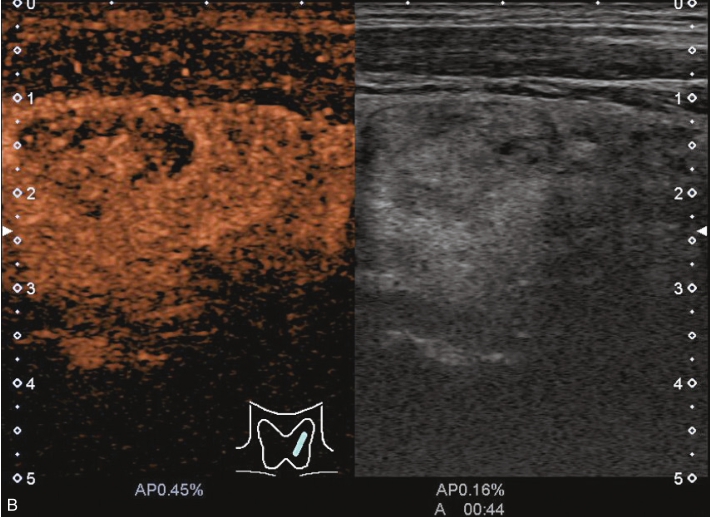

甲状腺右叶下极可见一低回声结节,紧贴甲状腺包膜,突出于甲状腺包膜,大小约0.82cm×0.72cm×0.55cm,呈椭圆形,边界清楚,内部为低回声,分布不均匀,后方回声稍增强,CDFI显示结节内未见明显血流信号,弹性成像示弹性评分为3分,见图1-3-11。

图1-3-11 甲状腺“木乃伊”结节

A、B、C、D.甲状腺“木乃伊”结节常规超声图像

经肘正中静脉团状注射造影剂SonoVue1.2ml后,13s周围甲状腺组织开始增强,病灶边缘部呈稍增强,病灶内部始终呈无增强,在整个造影过程中病灶内始终呈无增强,见图1-3-12、ER1-3-6。

“木乃伊”结节超声造影表现为无增强。

部分良性甲状腺结节囊液吸收后超声表现为低回声、缩小,超声表现为可疑恶性征像,二维超声表现与甲状腺乳头状癌难以鉴别,超声造影可以明确病灶内有无增强,提高诊断准确性。

图1-3-12 甲状腺“木乃伊”结节造影图像

A.造影示低回声结节呈无增强;B.增强晚期仍呈无增强